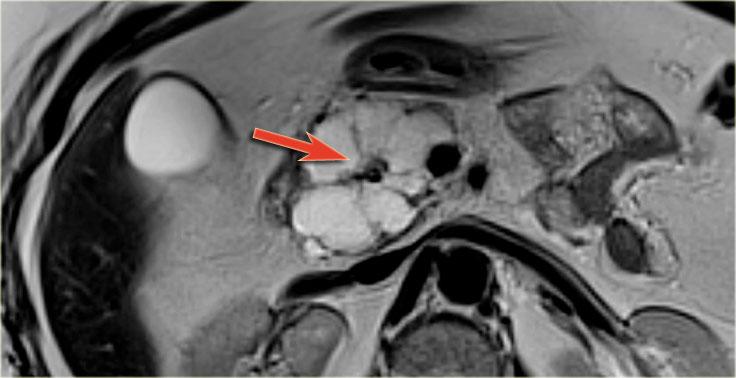

Hình ảnh cho thấy chuỗi xung T2W của bệnh nhân nam 71 tuổi có tiền sử sụt cân và các triệu chứng đau bụng trên không đặc hiệu.

Ban đầu được nghĩ đến là IPMN nhánh ống, nhưng kết quả hóa ra là SCN.

Lưu ý vùng giảm tín hiệu trung tâm.

Đây là mô sẹo trong SCN.

Cũng lưu ý bề mặt thùy múi đặc trưng.